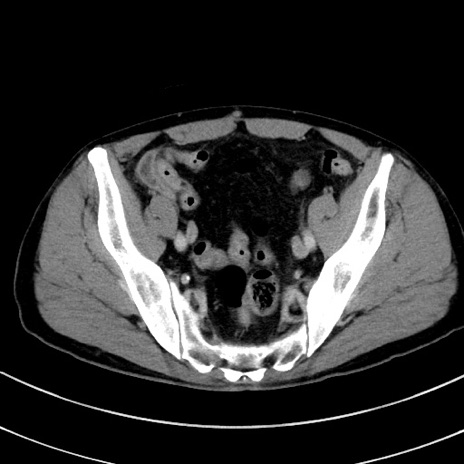

症例8(横断像)

【症例】 60歳代男性

【主訴】 黒色吐物

【現病歴】 4日前から嘔気自覚、2日前の朝食後にも嘔気あり、自分で手で嘔吐反射起こし嘔吐したところ血が混ざっていたため受診。

【既往歴】 5年前汎発性腹膜炎を伴う急性虫垂炎で手術、高血圧、前立腺肥大症、高脂血症

【身体所見】 腹部正中に手術癩痕あり 腹部平坦・軟圧痛なし膨満感あり

【データ】WBC 8400、CRP 4.54